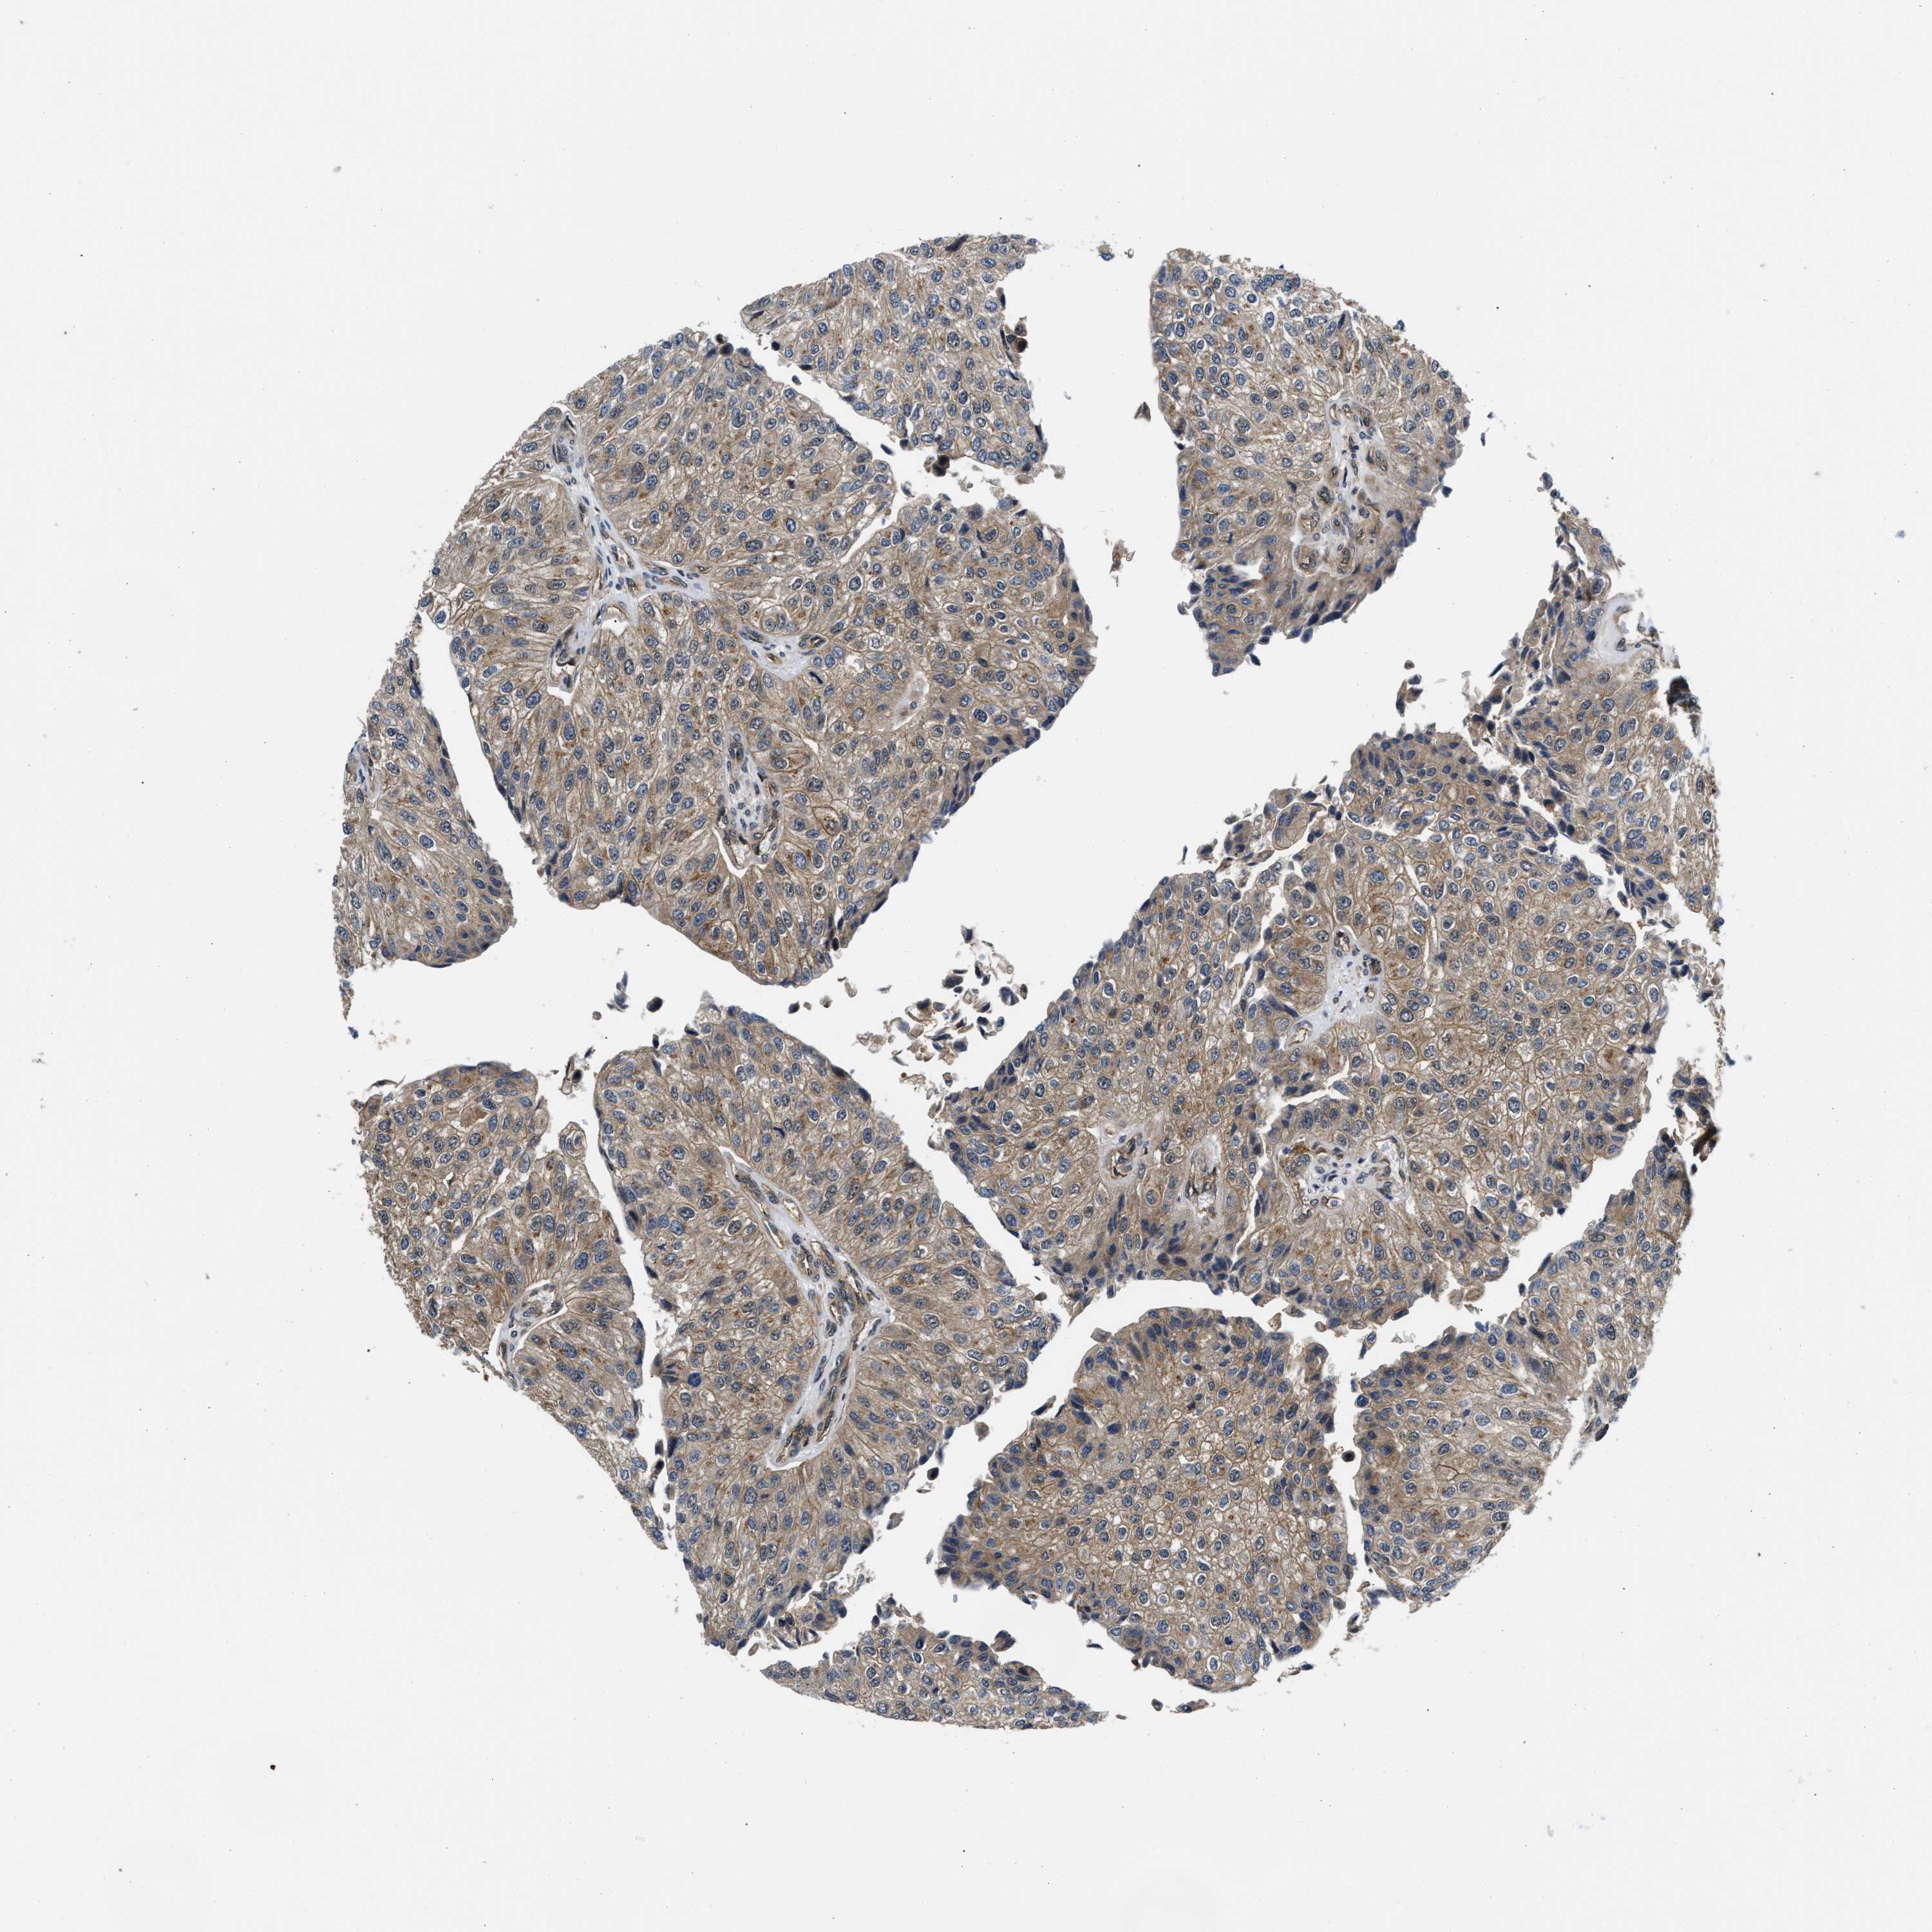

UROTHELIAL CANCER - Protein expressioni

A mouse-over function shows sample information and annotation data. Click on an image to view it in a full screen mode. Samples can be filtered based on level of antibody staining by selecting one or several of the following categories: high, medium, low and not detected. The assay and annotation is described here.

Note that samples used for immunohistochemistry by the Human Protein Atlas do not correspond to samples in the TCGA dataset.

Antibody stainingi

Antibody staining in the annotated cell types in the current human tissue is reported as not detected, low, medium, or high, based on conventional immunohistochemistry profiling in selected tissues. This score is based on the combination of the staining intensity and fraction of stained cells.

Each image is clickable and will lead to virtual microscopy that enables deeper exploration of all samples and also displays staining intensity scores, fraction scores and subcellular localization as well as patient and tissue information for each sample.

Antibody HPA016867

Antibody HPA018271

Urothelial carcinoma, Low grade

Urothelial carcinoma, High grade